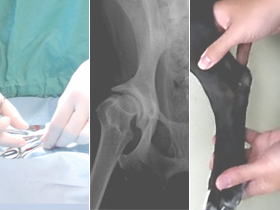

整形外科疾患徹底攻略シリーズ【診断編】 日本で飼育される犬や猫の寿命は延長傾向にあり、高齢化はこれからも進んでいくと思われます。 最近では、人においても高齢期の運動器疾患の重要性が認識され始めていて、運動障害に対しての関心が高まりつつあります。それに伴って、生活の質を改善させるまたは維持するための治療を望む声が増えてきており、家族は獣医師と一体となってチームを組んで対応していかなくてはならない時代になってきています。このような背景から、獣医師も運動器疾患の診断に精通しておく必要があります。 本公演を通じて、骨や関節を中心とした整形外科疾患や、その他に運動障害を生じる疾患の鑑別方法を習得し、明日からの診療の参考にして頂ければ幸いです。